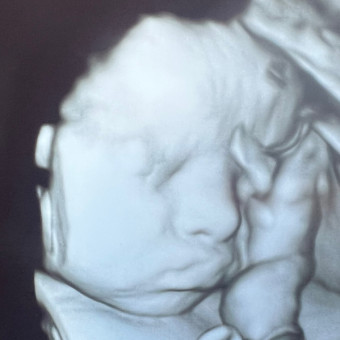

Baby Quinton’s Registry

Christopher & Brittany Clancy

Thank you so much for considering a gift for our baby boy. We are so excited to welcome him to the family.